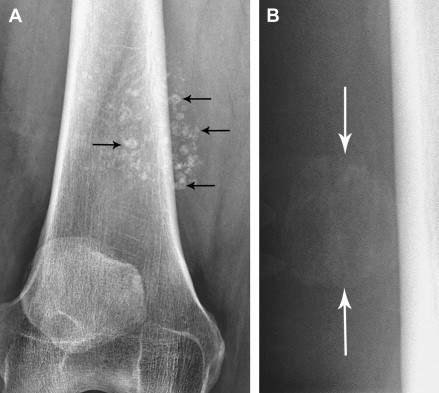

Loạn sản sụn và xương. Trẻ thường có vẻ bề ngoài thất thường, chân ngắn, tay ngắn, cổ tay, cổ chân bè, hộp sọ bất thường...